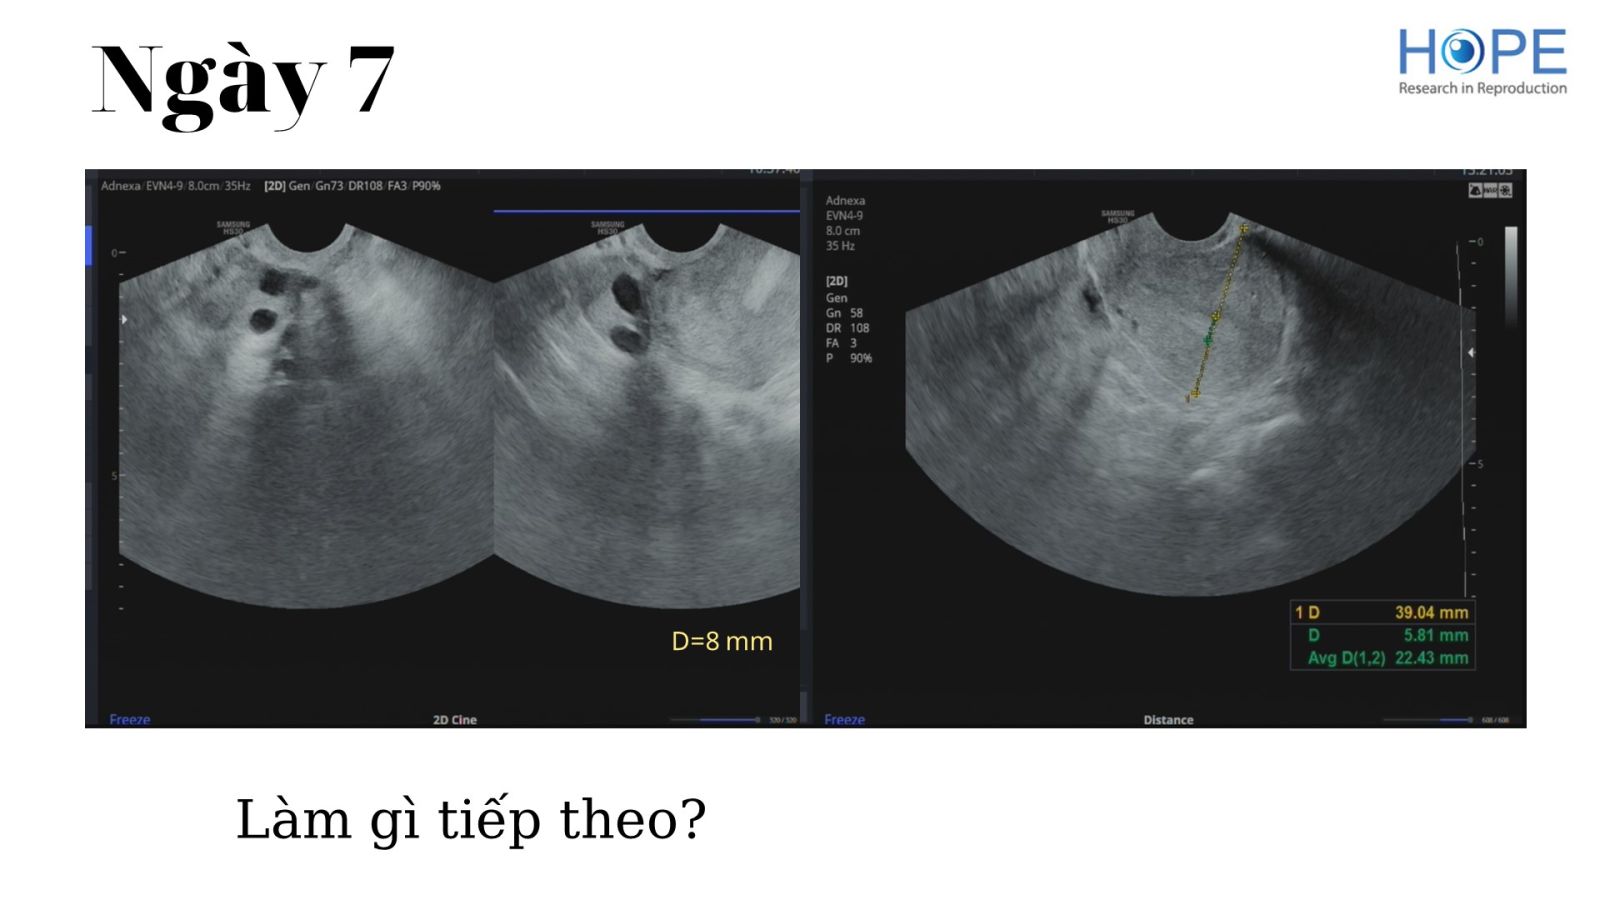

Các phác đồ kích thích buồng trứng nhẹ để IUI –  cách theo dõi kích thích buồng trứng

BS Lê Thị Hà Xuyên - IVFMD Phú Nhuận